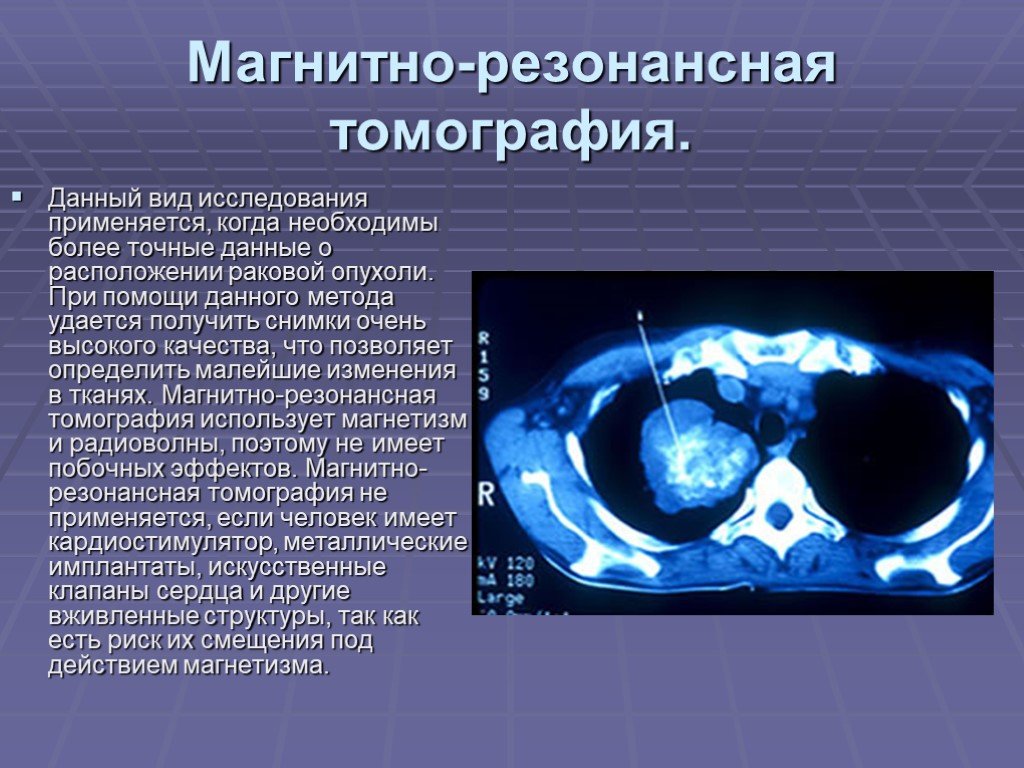

Периферическая карцинома легких кт. Периферический очаг легкого. Кт признаки периферического. Периферическое новообразование. Магнитно-резонансная томография легких. Магниторезонансная томография легких. Магнитно ядерная томография. Ядерно-магнитно-резонансная томография.

Магнитно-резонансная томография легких. Магниторезонансная томография легких. Магнитно ядерная томография. Ядерно-магнитно-резонансная томография. Саркома молочной железы на маммографии. Фибросаркома маммография. Саркома молочной железы рентген. Болезнь Педжета молочной железы маммография.